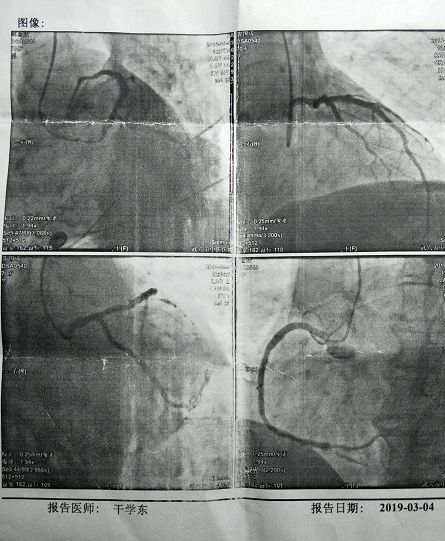

周日上午十點,一大早從武漢趕來的干教授來不及歇息就走進手術室導管室。我被安排第三個進導管室,沒有恐懼,也不緊張,因為這已經(jīng)不是頭部次了。了解這種微創(chuàng)手術,造影手術全在血管內(nèi)進行,而血管組織又沒神經(jīng),所以手術過程沒一絲疼痛。右手腕局部麻醉,橈動脈穿刺,插鞘管,注射造影劑……前后不到半小時,干教授那“行云流水”般的造影術,猶如魔術大師將秘密深處的冠狀動脈清晰地呈現(xiàn)在顯示屏上……

焦急的等待著,終于等到了干教授的診療報告:1、左主干血管正常,支架內(nèi)無狹窄,回旋支近段支架內(nèi)無狹窄;2、右冠狀動脈支架內(nèi)無狹窄,根據(jù)造影圖像。干教授認為沒必要植入支架,調(diào)整藥物進行后期治療。走出手術室,懸在心上的一塊石頭終于放下了。